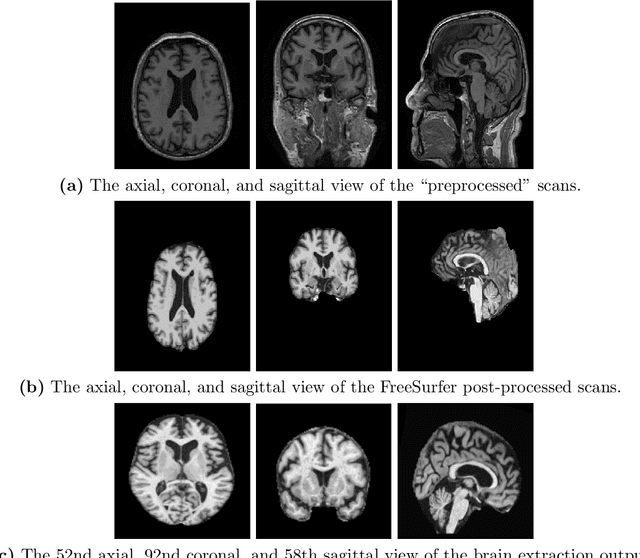

Abstract:A plethora of deep learning models have been developed for the task of Alzheimer's disease classification from brain MRI scans. Many of these models report high performance, achieving three-class classification accuracy of up to 95%. However, it is common for these studies to draw performance comparisons between models that are trained on different subsets of a dataset or use varying imaging preprocessing techniques, making it difficult to objectively assess model performance. Furthermore, many of these works do not provide details such as hyperparameters, the specific MRI scans used, or their source code, making it difficult to replicate their experiments. To address these concerns, we present a comprehensive study of some of the deep learning methods and architectures on the full set of images available from ADNI. We find that, (1) classification using 3D models gives an improvement of 1% in our setup, at the cost of significantly longer training time and more computation power, (2) with our dataset, pre-training yields minimal ($<0.5\%$) improvement in model performance, (3) most popular convolutional neural network models yield similar performance when compared to each other. Lastly, we briefly compare the effects of two image preprocessing programs: FreeSurfer and Clinica, and find that the spatially normalized and segmented outputs from Clinica increased the accuracy of model prediction from 63% to 89% when compared to FreeSurfer images.